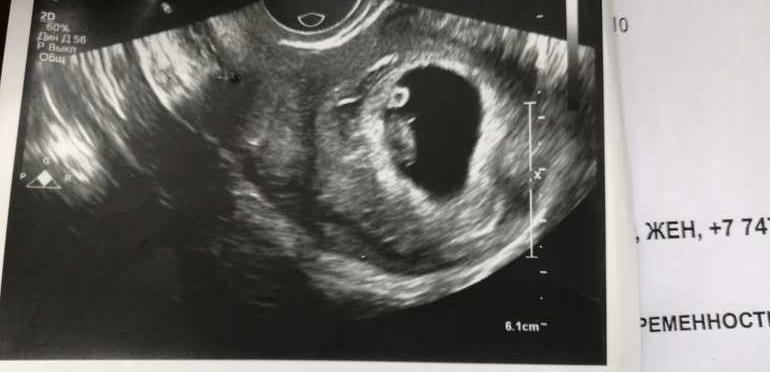

Для собственного спокойствия на 7 недели сходила на УЗИ, сердечко слышно все хорошо😍.